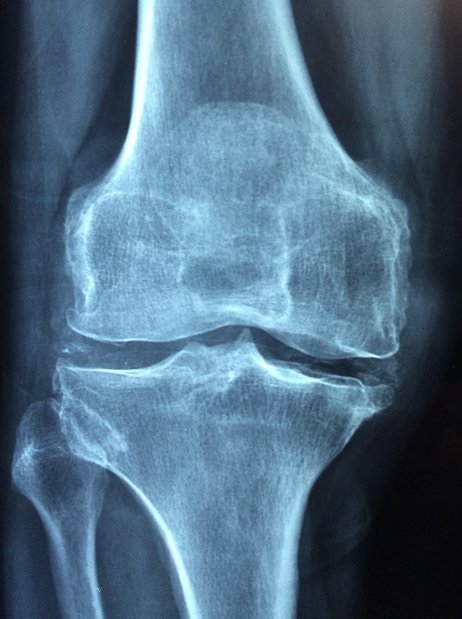

골다공증 - 이미지

골다공증은 뼈의 강도가 약해져 작은 충격에도 쉽게 골절이 발생하는 질환으로, 삶의 질을 크게 저하시킬 뿐만 아니라 심각한 합병증을 유발할 수 있습니다.